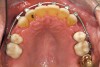

Figure 2a  Corticotomy SFOT. The patient presented with unesthetic anterior bridgework that was placed at age 14 to compensate for congenitally missing Nos. 7 and 10.

Figure 2a

Figure 2b  A corticotomy in SFOT is a surgical technique in which only the cortical bone is cut, perforated, or mechanically altered to the depth of the medullary bone and the medullary bone remains intact.

Figure 2b

Figure 2c  One week postsurgery with mesial buildups on Nos. 5 and 12 and thin pontics on archwire to conceal spaces during closure.

Figure 2c

Figure 2d  Prerestorative orthodontics was completed in 5 months. Final result 3 years, 4 months after completion.

Figure 2d

Figure 2e  Teeth Nos. 5 and 12 were converted to Nos. 6 and 11, and Nos. 6 and 11 were converted to Nos. 7 and 10. Nos. 4 and 13 were enlarged. Note stability and absence of orthodontic relapse. Before-and-after smiles.

Figure 2e

Figure 2f  Teeth Nos. 5 and 12 were converted to Nos. 6 and 11, and Nos. 6 and 11 were converted to Nos. 7 and 10. Nos. 4 and 13 were enlarged. Note stability and absence of orthodontic relapse. Before-and-after smiles.

Figure 2f

Figure 2g  Periodontist: Edward P. Allen, DDS, PhD. Prosthodontist: Robert R. Winter, DDS.

Figure 2g

Figure 2h  Periodontist: Edward P. Allen, DDS, PhD. Prosthodontist: Robert R. Winter, DDS.

Figure 2h